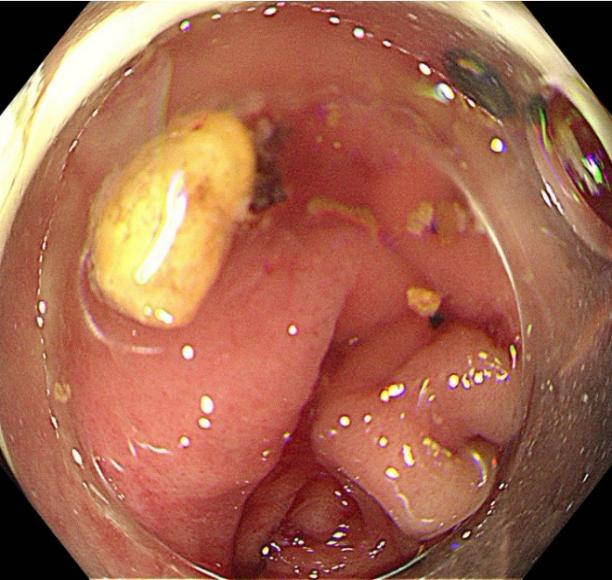

手术全程在高清内镜直视下进行,先将肠镜送至回盲部,定位阑尾开口后,小心翼翼地将子镜置入阑尾腔内。在高清内镜直视下,隐藏在阑尾里的粪石清晰可见。医护人员默契配合,利用专用取石器械,稳稳抓住粪石并缓缓取出。整个手术过程顺利,耗时短,创伤极小,患者全程不适。